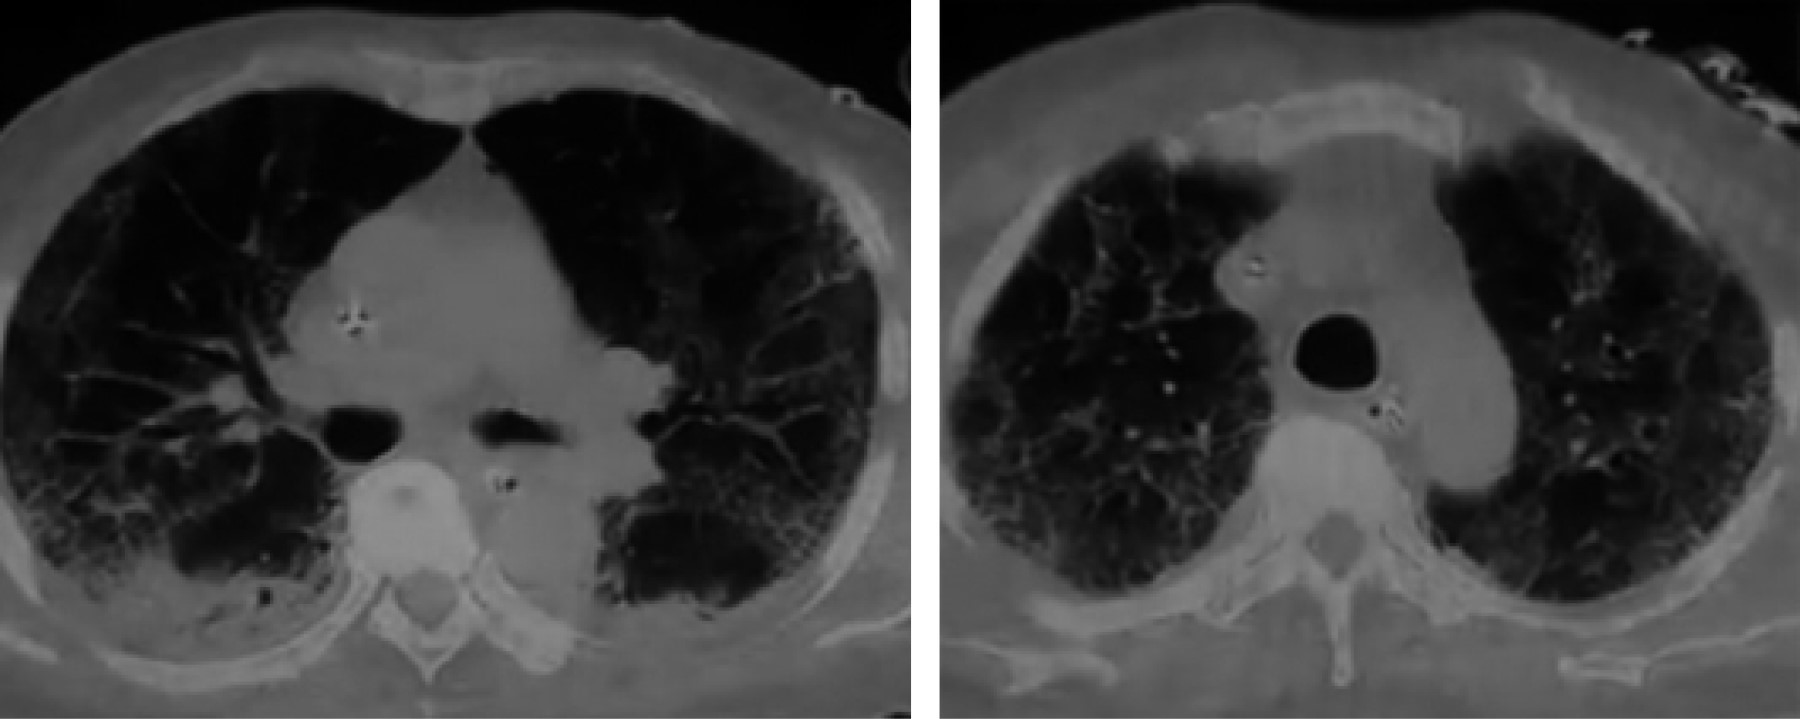

Reporte de gases arteriales con injuria pulmonar severa, PaFiO2 de 75, sin deterioro de la ventilación minuto alveolar, sin deuda bajo gasto ni sufrimiento mitocondrial. Se implementó cánula de alto flujo con un pico en su nivel de 60 y FiO2 de 100%, con el ánimo de implementar inertancia por presión y temperatura. Fue llevado a escanografía de tórax, que documentó infiltrados en cuatro campos pulmonares, en vidrio esmerilado con colapsos posterobasales (Figura 1).

Figura 1